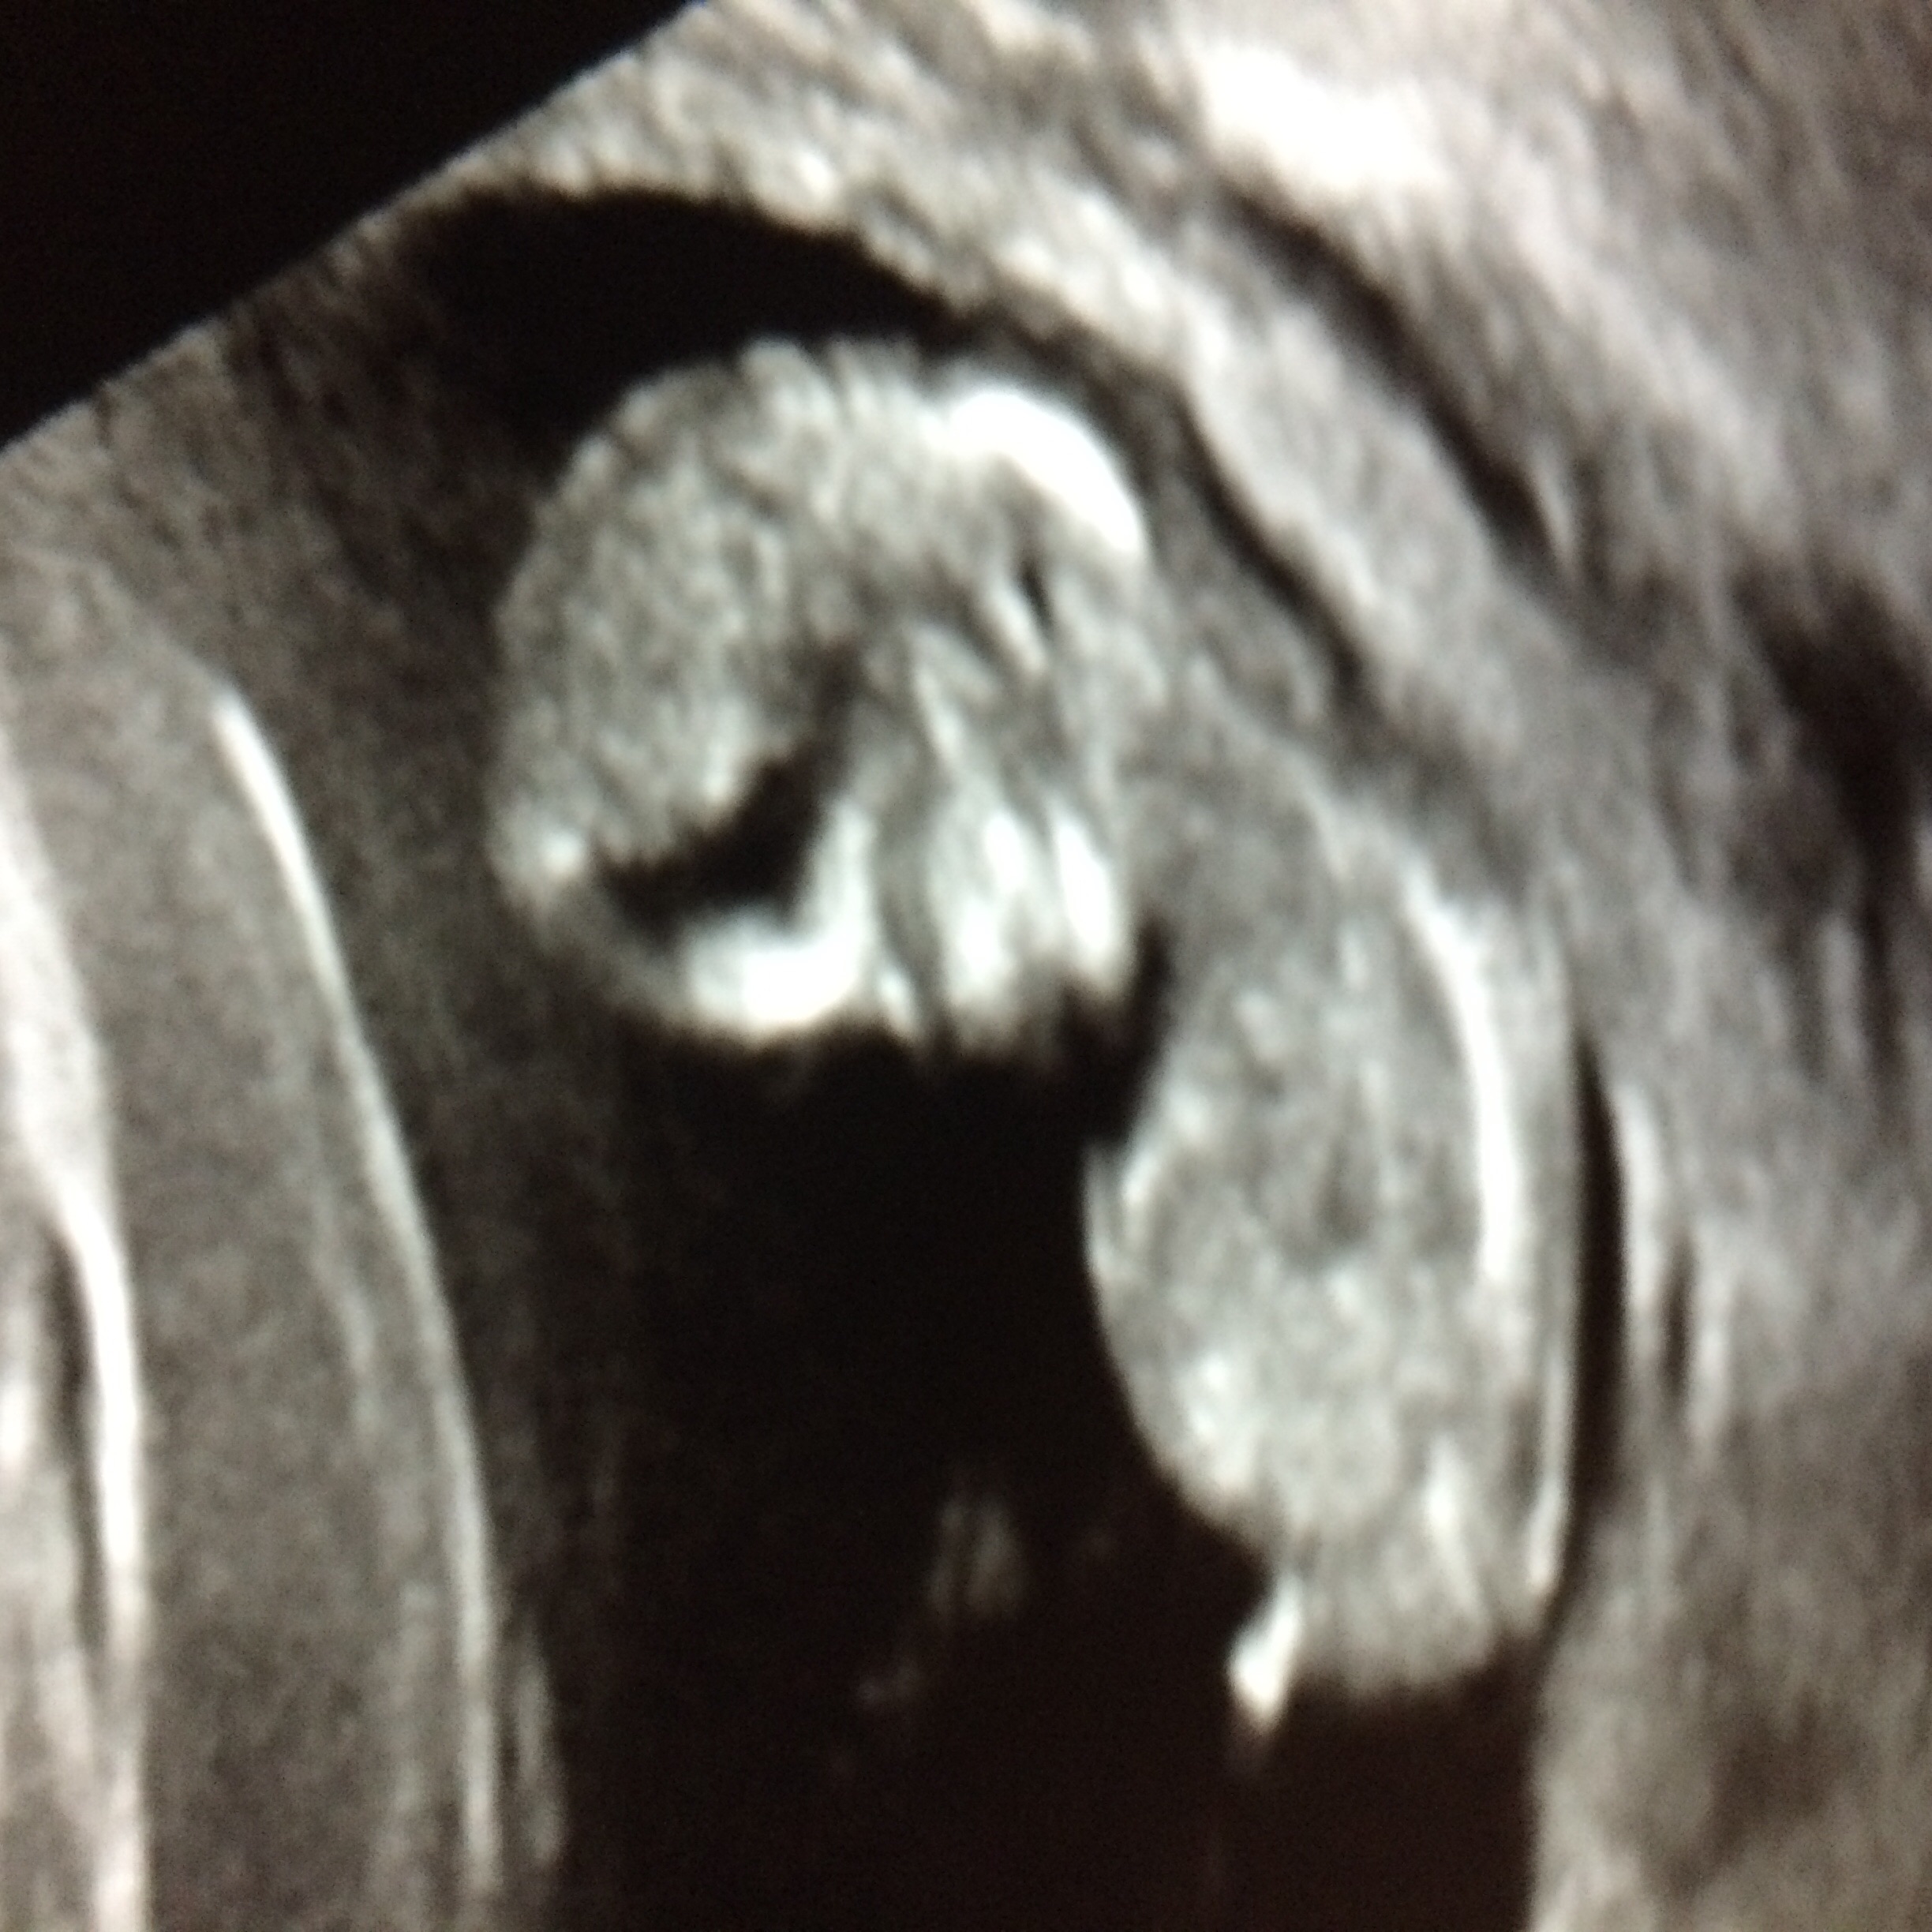

Is the nub mobile? I have some photos with it flat. So confused.

It does look blue but yes it is mobile. I have a great little video of my DS3 at 12 weeks with his little winky flapping around as he kicks lol. Post your others too :)

These are all same baby lol between 12-12/6